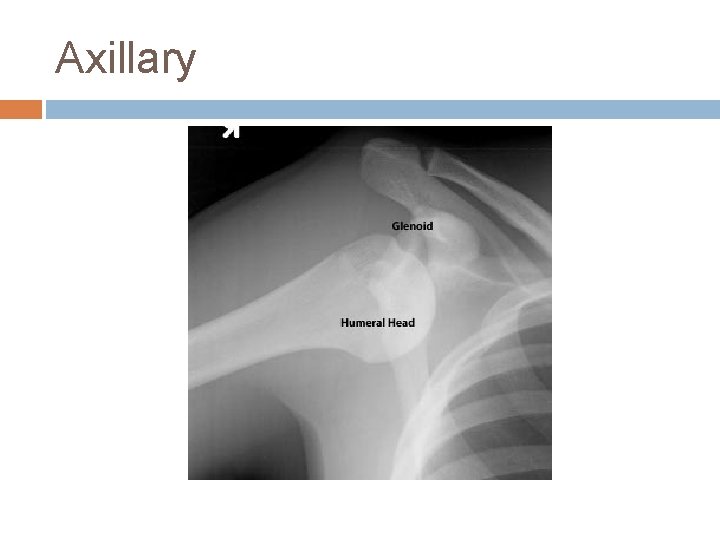

Axillary

Anterior Instability Exams-Apprehension -Relocation -Load and Shift Diagnostics-X-ray Views: AP, axillary and scapular-Y -can be performed before for diagnosis or after reduction for confirmation of relocation depending on clinical setting